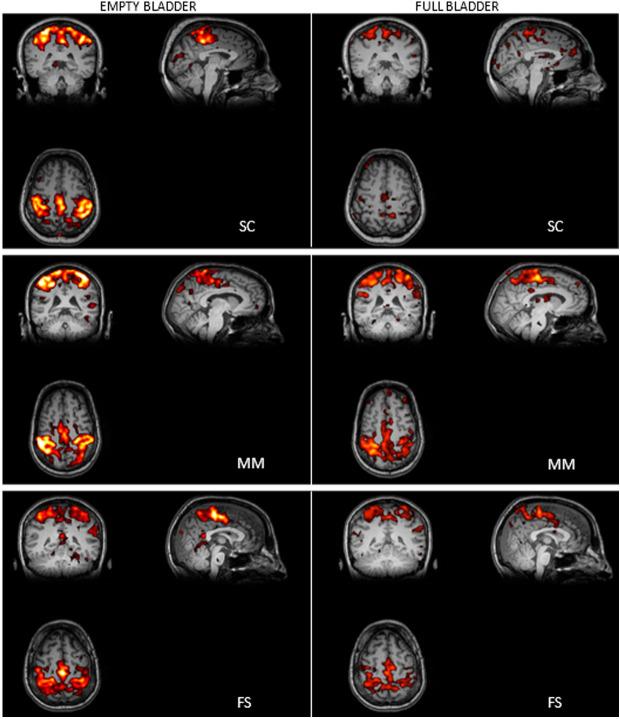

Bladder pain syndrome/Interstitial cystitis (BPS/IC) is characterized by increased activity in bladder afferent pathways, recruitment of silent nociceptive neurons, and sensitization of the brain areas responsible for pain amplification. Default mode network (DMN) is a set of regions activated during the resting state, which reflect the brain's intrinsic activity. Conversely, the sensorimotor network (SMN) plays a key role in structural neuroplasticity. This study aimed to evaluate DMN and SMN activity in BPS/IC patients, both with and without bladder noxious stimulus, using functional brain magnetic resonance imaging (MRI). Six BPS/IC female patients underwent 3 Tesla fMRI brain scanners. Acquisitions consisted of 10-minute blood oxygen level-dependent echo-planar imaging. The first acquisition was with an empty bladder, painless, and the second was with suprapubic pain. Data were processed using the independent component analysis method with the MELODIC tool from the functional brain MRI of the Brain Software Library (FSL). A semi-quantitative analysis was performed afterward. The patients' age was 42.6 ± 5 years, pain intensity was 7 ± 0.7 (0-10), day and night frequency were 9.2 ± 2.2 and 2.8 ± 1.0, and maximal bladder capacity was 260 ± 54 mL. One patient was unable to complete the study. All patients showed a comparable DMN activation in both empty and full bladder states, and all presented high SMN activation whether the bladder was empty or full. The activation of DMN at both bladder states, empty and full, and constant SMN activation without and with pain supports the role of these networks in BPS/IC. Similar findings have been reported in other chronic pain syndromes.

膀胱疼痛综合征/间质性膀胱炎(BPS/IC)的特征是膀胱传入通路活动增加、沉默伤害性神经元的募集以及负责疼痛放大的脑区敏化。默认模式网络(DMN)是一组在静息状态下被激活的区域,反映大脑的内在活动。相反,感觉运动网络(SMN)在结构神经可塑性中起关键作用。本研究旨在使用功能性脑磁共振成像(MRI)评估有无膀胱有害刺激的BPS/IC患者的DMN和SMN活动。六名BPS/IC女性患者接受了3特斯拉功能磁共振成像脑扫描仪检查。采集包括10分钟的血氧水平依赖回波平面成像。第一次采集时膀胱为空,无痛,第二次采集时伴有耻骨上疼痛。使用来自脑软件库(FSL)的功能性脑MRI的MELODIC工具通过独立成分分析方法处理数据。随后进行了半定量分析。患者年龄为42.6±5岁,疼痛强度为7±0.7(0-10),白天和夜间排尿频率分别为9.2±2.2和2.8±1.0,最大膀胱容量为260±54毫升。一名患者无法完成研究。所有患者在膀胱空虚和充盈状态下均表现出相当的DMN激活,并且无论膀胱空虚还是充盈,所有患者均表现出较高的SMN激活。膀胱空虚和充盈两种状态下的DMN激活以及有无疼痛时持续的SMN激活支持了这些网络在BPS/IC中的作用。在其他慢性疼痛综合征中也报道了类似的发现。